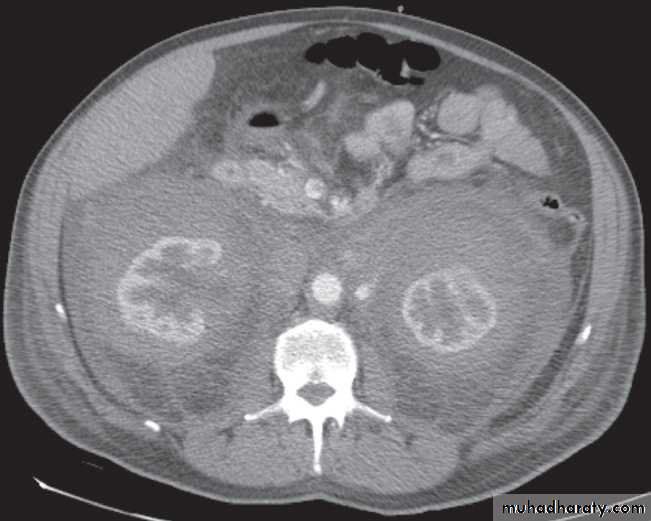

-Renal cell carcinomas are approximately spherical and often lobulated .With density similar to renal parenchyma or slightly less with often seen some areas of necrosis & calcification .

Staging of renal cell carcinoma is usually undertaken with CT, the current method of choice .